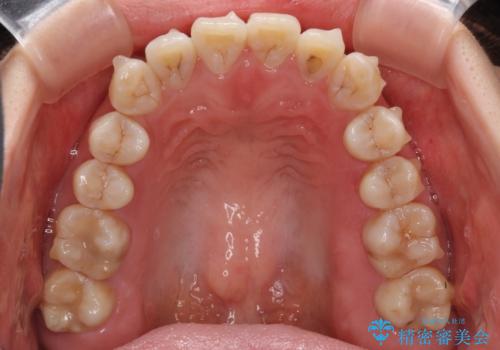

話しにくいオープンバイト インビザラインによる矯正治療

- 前歯の上下スペースによる話しにくさを気にして来院された患者様です。

インビザラインにより上下の前歯の隙間を閉じていくこととしました。

上下の奥歯を圧下させるようにすることで、前歯を接触させるように計画しました。

隙間に舌が入り込むことが話しにくさに繋がっていたため、舌の筋肉のトレーニングも並行して行い、話しにくさの改善と後戻りの抑制を図りました。